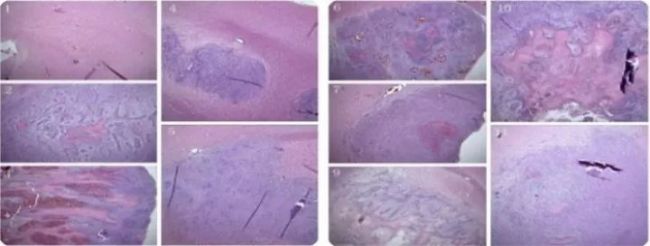

紋狀體腫瘤:

病理染色: